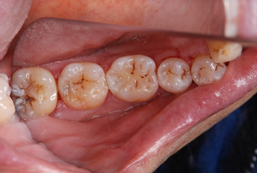

クリアフィル マジェスティ ESフロー(クラレノリタケデンタル)もその1つです(図1)。

3タイプ(Low, Super Low, High)ありますが、個人的にはLowタイプのシェードA2と A3を主に使っています。

操作性に優れ、形態付与も容易で、審美的にもたいへん良い材料です。

十分な機械的強度を有しているため、これまではペーストタイプを使っていた臼歯部咬合面のCR修復でも問題なく使えます(図2参照)。

図1 クリアフィル マジェスティ ESフロー(Lowタイプ)。